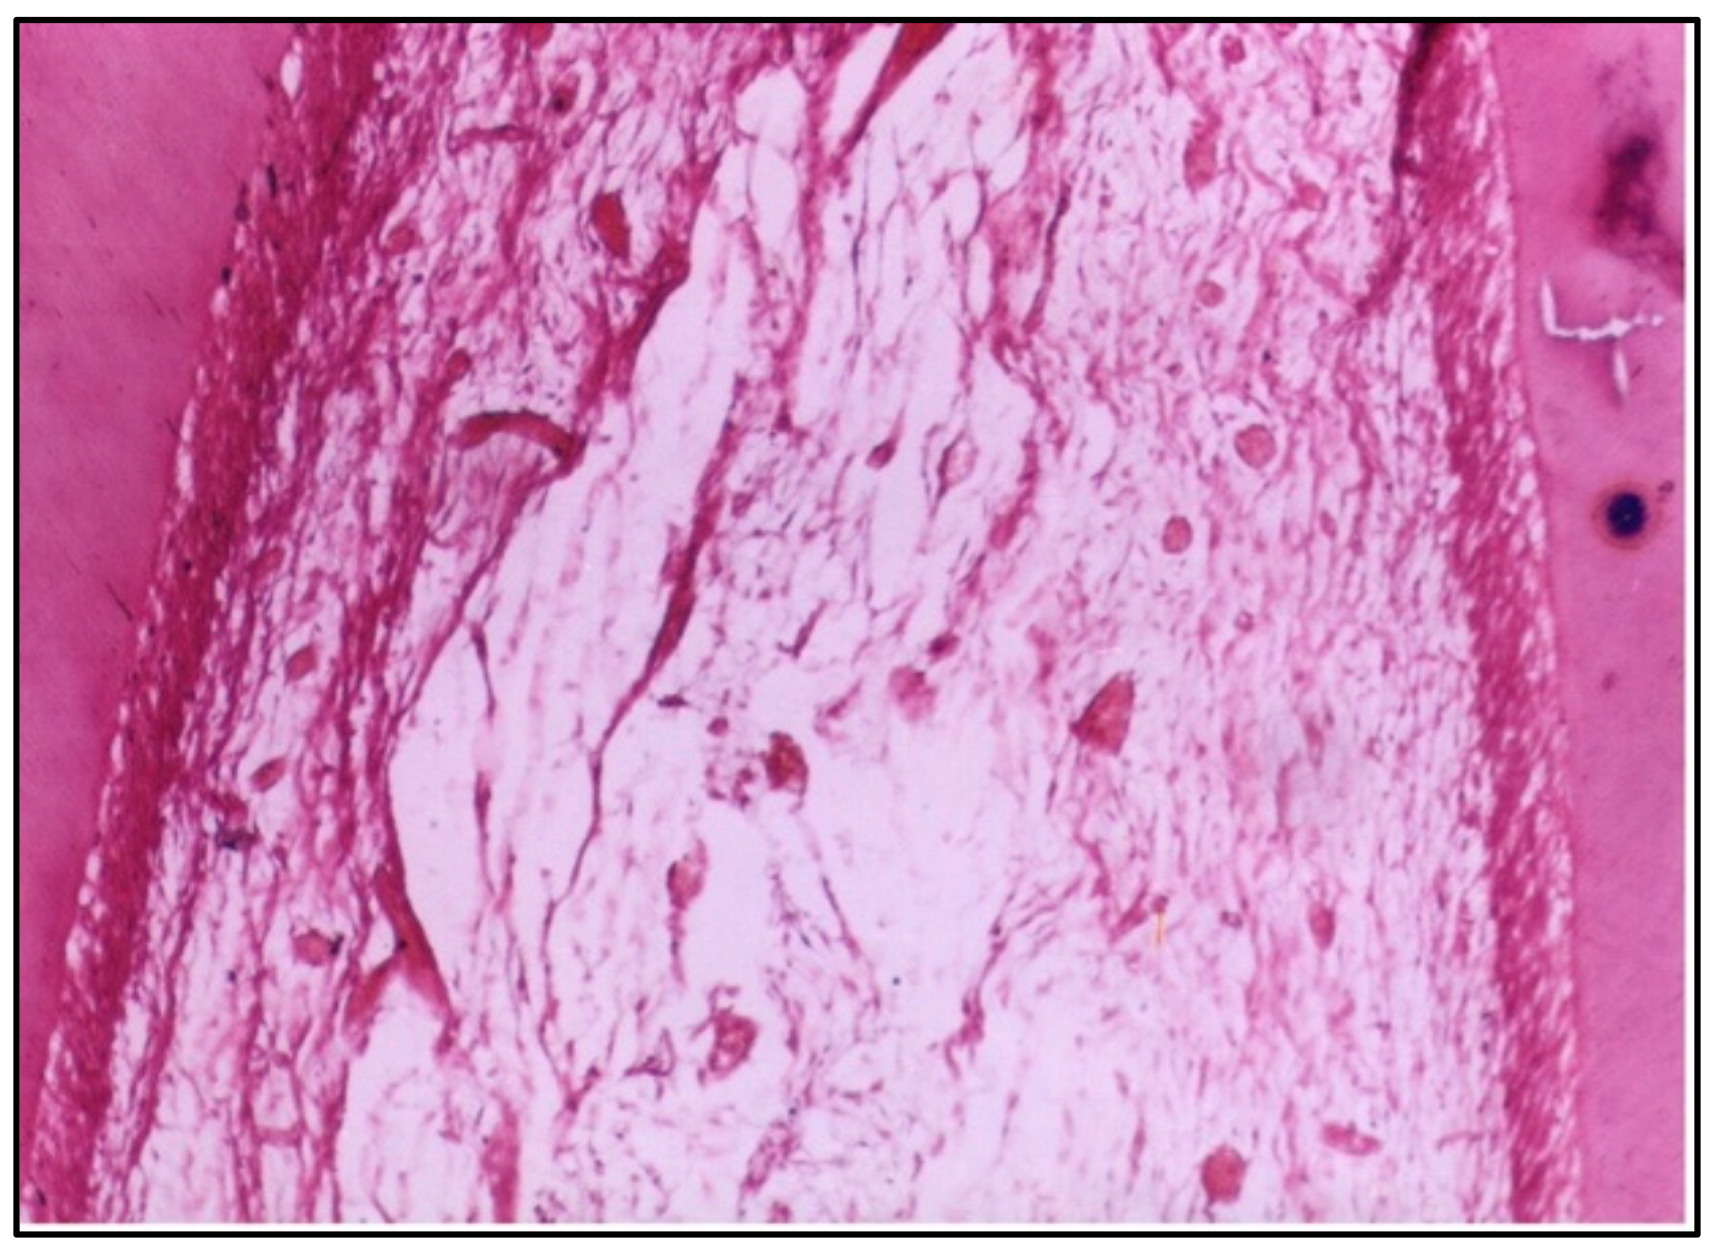

At 2 weeks, the specimens exhibited notable changes in the pulp tissue. The odontoblasts, which are the cells responsible for forming dentine, showed disorganization, indicating a disruption in their usual structure and function. There was also an increase in the vascular supply, suggesting an inflammatory response. The budding of new capillaries likely reflects the body’s attempt to repair or regenerate tissue. This reaction is typical of a mild to moderate inflammatory process following irritation or injury caused by the restorative material (Figure 1).

Regarding polyacid-modified composite resin, at 2 weeks, the specimens tested exhibited disorganization of odontoblasts and increased the vascular supply, indicated by the budding of new capillaries. This suggests an initial inflammatory response, possibly due to the material’s composition or the polymerization process. The increased vascularity can be interpreted as a reparative attempt by the pulp tissue to maintain homeostasis and facilitate healing [17].

Figure 1. Longitudinal section (LS) of the pulp (Group I, 2 weeks), showing disorganization of odontoblasts and an increase in the vascular supply to the pulp with the budding of new capillaries (H & E Stain, ×100).